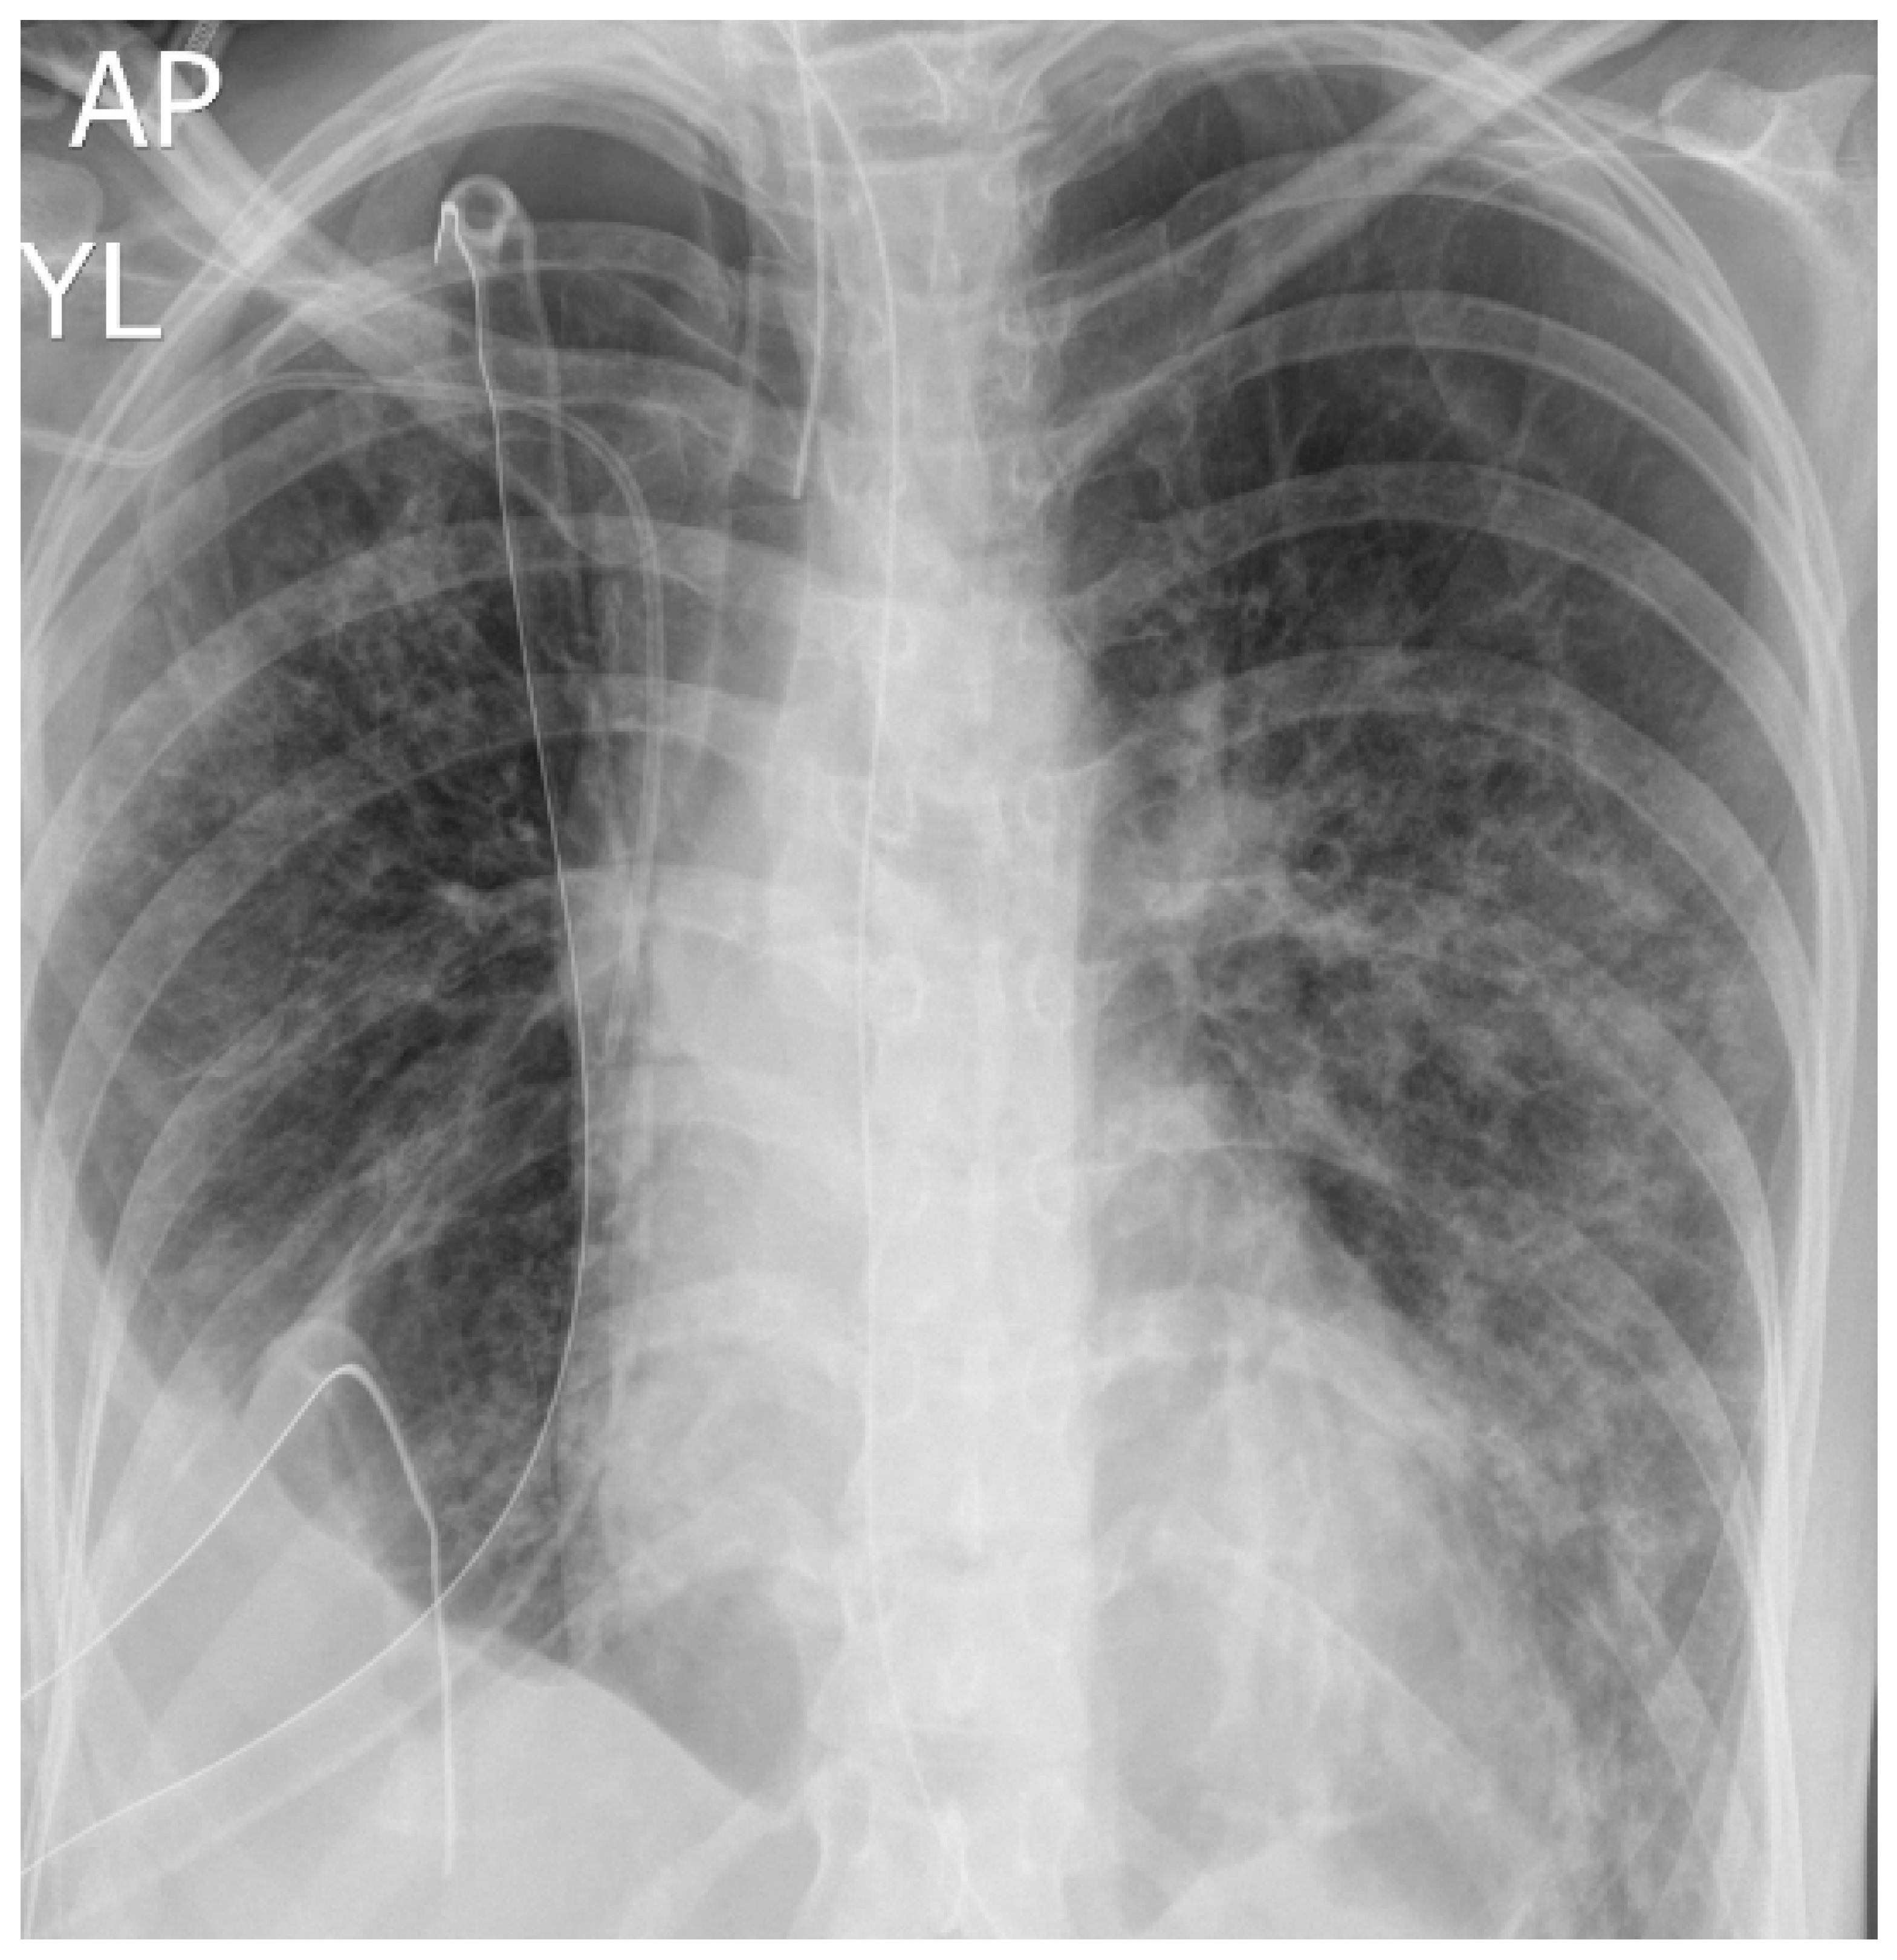

After extubation, despite intensive kinesiotherapy, the patient presented an ineffective cough, leading to the accumulation of secretions in the respiratory tract and increasing respiratory effort with desaturation. The patient was intubated and mechanical ventilation was started. After intubation, a significant amount of serous content was aspirated from the airway. Bronchofiberoscopic cleaning of the bronchial tree performed on subsequent days revealed a patent bronchus intermedius and residual mucous content, which was aspirated. On the eighth day, the patient was extubated again, followed by passive oxygen therapy via a face mask. Due to repeated respiratory areflexia, secretion retention in the respiratory tract, and increased respiratory effort and desaturation, the patient was reintubated after approximately 38 h and mechanical ventilation was started. In the double drainage of the right pleural cavity, a decreasing value of leakage of the respiratory mixture was observed, and as a result the drain from the right pleural cavity was removed on the ninth day. Due to the progression of the right-sided pneumothorax visible in the follow-up chest X-ray, the patient was consulted by a thoracic surgeon again and drainage of the right pleural cavity was performed to observe the leakage of the respiratory mixture. The aforementioned chest X-ray is presented in Figure 3.

Figure 3. Chest X ray of patient 1 during treatment—progression of right-sided pneumothorax, which resulted in drainage of right pleural cavity.